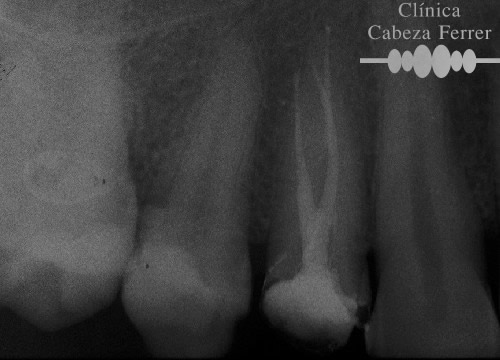

| Antes | Después |

En primer lugar se explora la pieza y se realiza un estudio radiológico. Si es necesario se pone anestesia local y se aísla en diente para mantenerlo limpio y seco durante el tratamiento. A continuación con el instrumental adecuado se realiza un orificio en la corona del diente y a través de él, mediante unos pequeños instrumentos llamados LIMAS, se extrae la pulpa. Posteriormente la cámara pulpar y los conductos radiculares se limpian, se esterilizan, se rellenan y se sellan herméticamente. Con un control radiológico se comprueba que el tratamiento se ha realizado correctamente. Ahora es el momento de reconstruir la anatomía del diente y si es necesario recubrirle con una corona para evitar su posterior fractura. En la mayoría de los casos, la endodoncia se realiza en una sola sesión.